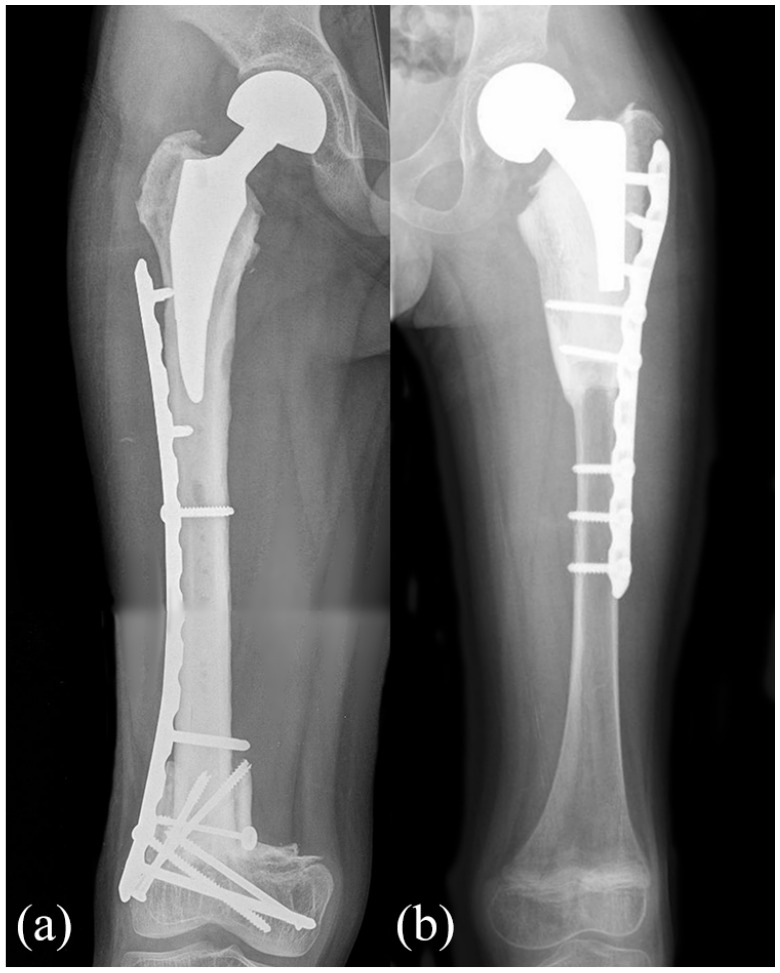

Methods: We reviewed 10 pediatric patients treated with proximal femur resection for a primary bone tumor and reconstruction with short stem allograft-prosthesis composite, with at least 24 months follow-up. The median age was 9 years (4-13) at surgery. The mean resection length was 15 cm (6-29). In six cases, fixation was performed with a short plate positioned under the great trochanter while in four cases a long plate extended over the great trochanter was employed.

Results: Nine complications that required surgical revision were assessed in six patients (one wound dehiscence, two nonunions, two fractures, one acetabular wear, three hypometria), while allograft-prosthesis composite removal was required in three patients. The revision-free survival was 57% (95% confidence interval 33%-100%) at 5 and 10 years. The graft removal-free survival was 75% (95% confidence interval 50%-100%) at 5 and 10 years. The mean Musculo-Skeletal Tumor Society Score was 28 (20-30).